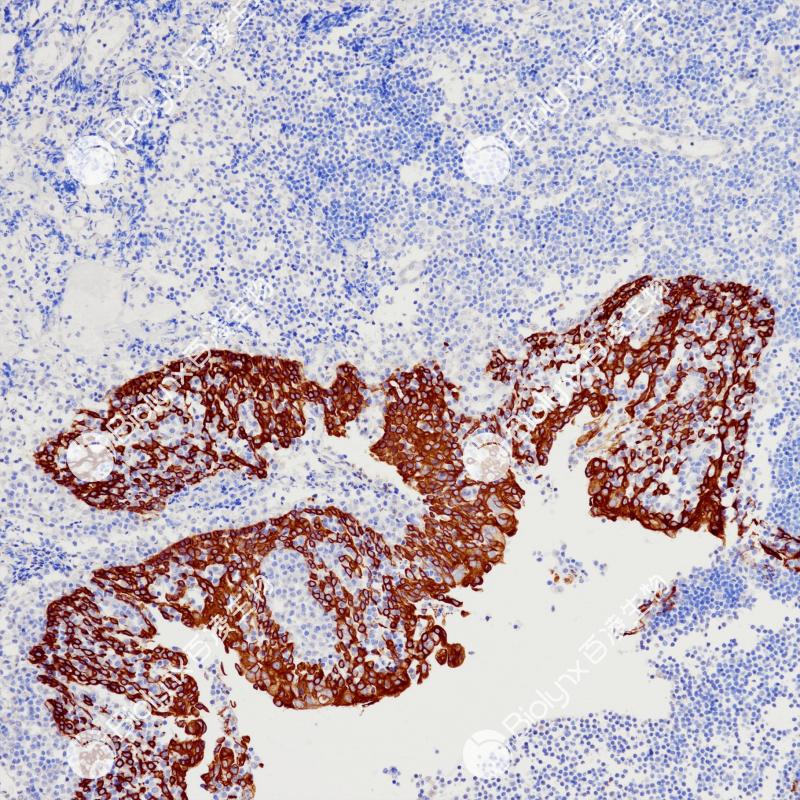

宫颈癌CK5&6(BP6252)染色

CK5&6

细胞角蛋白5&6是一种基底细胞角蛋白,在正常组织鳞状上皮和导管上皮的基底细胞以及部分的鳞状上皮生发层细胞、肌上皮细胞、间皮细胞表达阳性,腺上皮细胞表达阴性。该抗体主要用于鳞癌与腺癌、间皮瘤与腺癌的鉴别诊断,也可用于导管上皮良恶性增生的鉴别。

阳性对照

宫颈癌

亚细胞定位

细胞质

稀释比

1:100-1:200